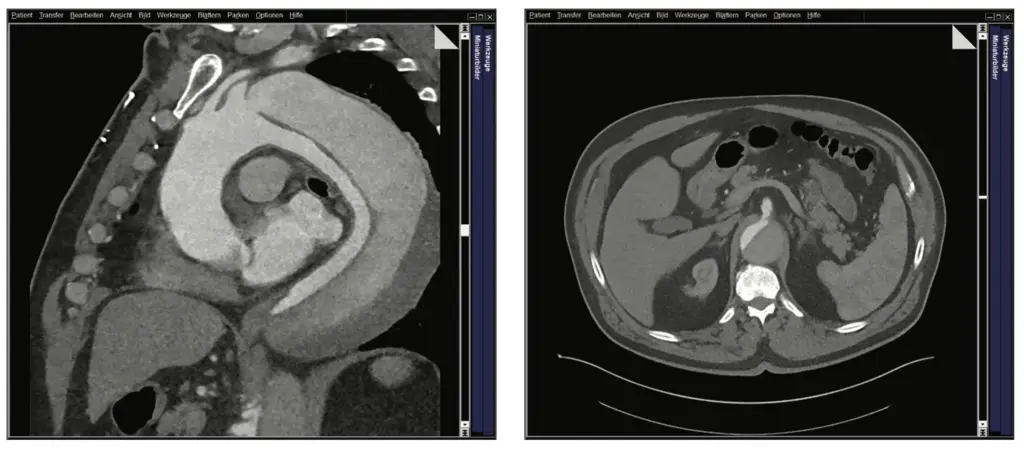

Im Herbst 2023 wurde bei dem damals 62-jährigen Mann als Zufallsbefund im Rahmen einer urologisch veranlassten CT-Untersuchung eine komplexe thorakoabdominelle Aortendissektion Typ Standford B diagnostiziert. Distal setzte sich die Dissektion in ein mutmaßlich vorbestehendes infrarenales Aortenaneurysma fort und bildete ein Aneurysma dissecans von 8 cm Durchmesser. Die Dissektion endete in der linken A. iliaca externa. Zudem bestanden Aneurysmata der A. iliaca externa. Das wahre Lumen war schmächtig im Sinne eines subtotalen True-Lumen-Kollaps.

In interdisziplinären Fallkonferenzen wurden die möglichen Versorgungsoptionen diskutiert und schließlich fiel unter Einbeziehung des Patienten die Entscheidung zu einer dreizeitigen endovaskulären Versorgung. Zunächst erfolgte eine Versorgung der thorakalen Aorta mittels Stentgrafts, die proximale Landezone musste dabei nach vorherigem Debranching mittels Carotido-Carotido-Subclavia-Bypass bis in die Zone 1 nach Ishimaru ausgeweitet werden. Distal erfolgte eine Versorgung der Dissektion der Beckenarterien mit Ausschaltung der Iliacalaneurysmata durch eine beidseitige Implantation eines Iliac-Side-Branch-Devices (Abb. 1 a–c).

Trotz dieser positiven Befunde wurde ein langer intensivstationärer Aufenthalt notwendig, da es postoperative Komplikationen wie ein akutes Nierenversagen, eine Pneumonie und ein Delir gab. Allerdings entwickelte sich der Gesamtverlauf schließlich positiv und der Patient konnte über die Reha in die Häuslichkeit entlassen werden. Bildgebend waren die Aneurysmata (abgesehen von einem kleinen Typ 2 Endoleak) ausgeschaltet und die Dissektion regelhaft angelegt. Die Stentgrafts waren einschließlich der viszeralen und iliacalen Branches regelhaft perfundiert (Abb. 5 a und b).